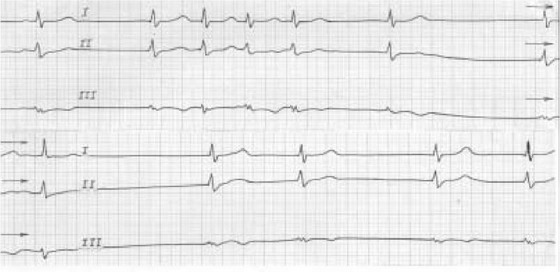

Рис. 93.

Пауза сердечного ритма при дисфункции синусового узла (холте-ровское мониторирование ЭКГ). Рис. 94. Дисфункция синусового узла в виде тахикардии-брадикардии:

Рис. 94.

Дисфункция синусового узла в виде тахикардии-брадикардии: узловой медленный ритм с частотой 47 в мин сменяется залпом (второй-пятый комплексы) суправент-рикулярной тахикардии с частотой 145 в мин.